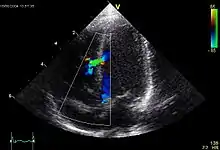

![]() Echokardiogramm eines ASD II, d.h. Ostium-secundum-Typ. |

Atrial septal defect (ASD)

ASD II:

Das heruntergewachsene Septum primum reisst normalerweise in der Mitte ein und bildet das Foramen secundum bzw. Foramen ovale. Dieses wird durch das links vom Septum primum ebenfalls von oben herunterwachsende Septum secundum gardinenartig bedeckt (Ventil) und kurz nach der Geburt durch Umkehr der Druckverhältnisse funktionell (z.T. strukturell durch Verklebung) verschlossen. Ist der Verschluss so ungenügend, dass es zum Links-rechts-Shunt kommt, spricht man vom offenen Foramen ovale bzw. ASD II. Der ASD II ist im Ggs. zum ASD I weiter oben lokalisiert. Er macht oft wenig Symptome und wird oft erst im Erwachsenenalter erkannt. Der Links-Rechts-Shunt kann im EKG zu Zeichen der Rechtsherzbelastung führen (Rechtslagetyp, P pulmonale, inkompletter Rechtsschenkelblock ohne Hypertrophie-Zeichen (rsr's') als Zeichen der rechtsventrikulären Volumenbelastung) und bei starker Ausprägung zu klinischen Symptomen führen.